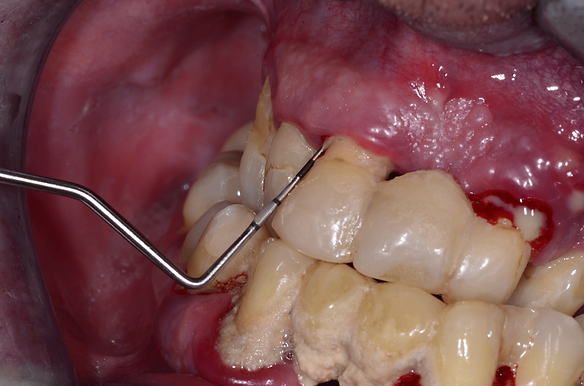

W badaniu podczas zapalenia dziąseł obserwuje się zaczerwienienie, obrzęk dziąseł oraz krwawienie występujące podczas szczotkowania, nitkowania zębów lub delikatnego badania sondą peridontologiczną.

Dlatego sonda periodontologiczna to najważniejszy instrument na tacy zabiegowej higienistki.

Służy do oceny:

- głębokości kieszeni przyzębnych,

- grubości dziąsła,

- pomiaru recesji dziąsłowej, utraty przyczepu,

- badania kamienia poddziąsłowego

- oraz obliczania parametrów zapalenia dziąseł – wskaźników.